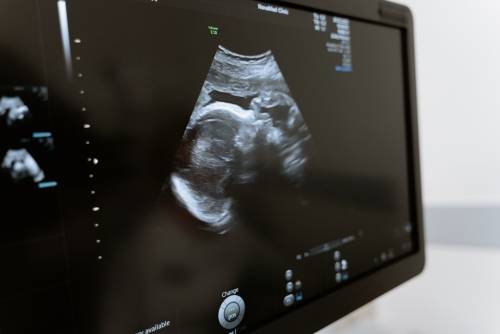

超声介入检查心脏,通常是指通过心脏腔内超声检查来诊断心脏疾病的方法。检查时需要放置引导管进入心脏,然后通过显示器观察心脏的结构、血流情况,以及是否存在异常病变等。